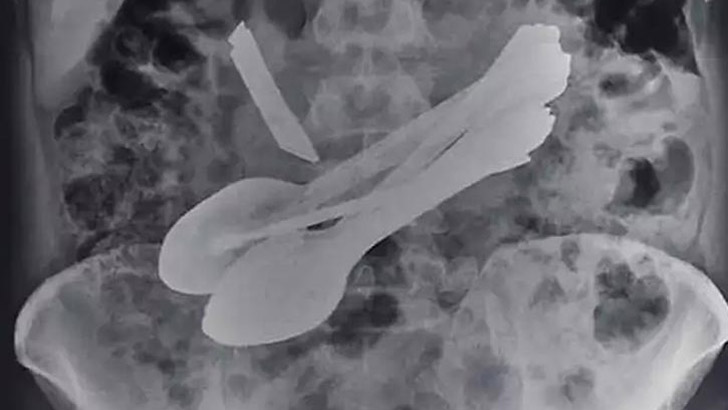

এর পর এক্স-রে করে দেখা যায়, তার পেটে ছুরির ফলাটা উঁচু হয়ে আছে। যখন আমরা অপারেশন করলাম তখন সেখান থেকে ছুরি ছাড়াও ৮টি চামচ, দুটি স্ক্রুড্রাইভার, দুটি টুথব্রাশ ও একটি স্টিলের বার বের করা হয়।